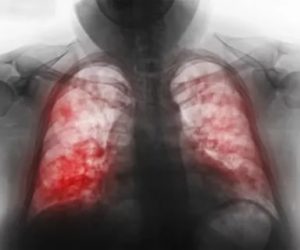

- – более точные методы. Различные формы туберкулеза выглядят по-разному на рентгенограммах (на фото). Например, при диссеминированной форме на легких имеются множественные, мелкие очаги затемнения с четкими границами, инфильтративный туберкулез затрагивает чаще всего верхние доли легких и на снимках проявляется в виде белесых затемнений с неровными краями. Очаговый туберкулез проявляется в виде затемнений диаметром до 2 сантиметров округлой формы, которые могут сливаться. Компьютерная томография обнаруживает маленькие очаги до 1 мм, позволяет рассмотреть изменения в тканях, установить форму туберкулеза, а также изучить лимфоузлы, которые не всегда заметны на рентгене.